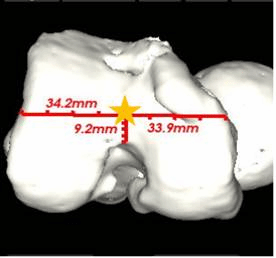

(图一)通过AIJOINT进行术前精准定位

(图二)模拟截骨后假体安放